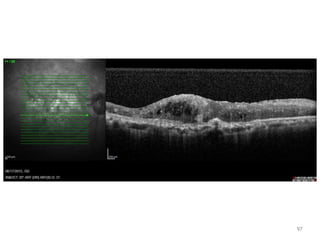

98

99

100